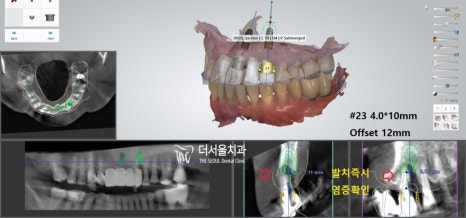

“ 역시나 앞니임플란트 케이스에도

컴퓨터 분석이 빠질 순 없죠? ”

(성남치과추천)

실제 구강 내를 본을 뜬 다음

인접치, 해부학적 조직과의 모든 관계를

꼼꼼히 파악해주는 똑똑한 친구입니다.

3차원으로 분석을 마친 뒤에는

제작된 가이드를 사용하여 식립을 마쳤습니다.